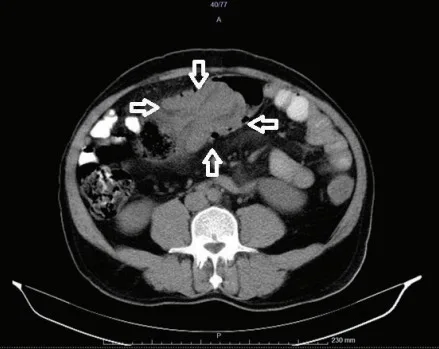

哎呀,说到这个肠套叠CT图,真是让人心惊胆战的!你知道吗,那种图一出来,医生们一个个都皱起了眉头,像是看到了什么不得了的大问题。我记得有一次,一个小朋友的家长拿着那张CT图来找我,脸上的表情比哭还难看。他们说,孩子肚子疼得厉害,做出来的CT图上,肠子就像是一条扭成了麻花的小蛇,真是让人看了心疼。

那图上的肠子,一层套一层,就像是玩偶里的小人儿,一个套一个,看得人眼花缭乱。医生说,这种情况要是不及时处理,孩子可是会有生命危险的。听到这话,家长的腿都软了,眼泪止不住地往下掉。我看着他们,心里也是五味杂陈,只能安慰说,医生们会尽全力救治的。